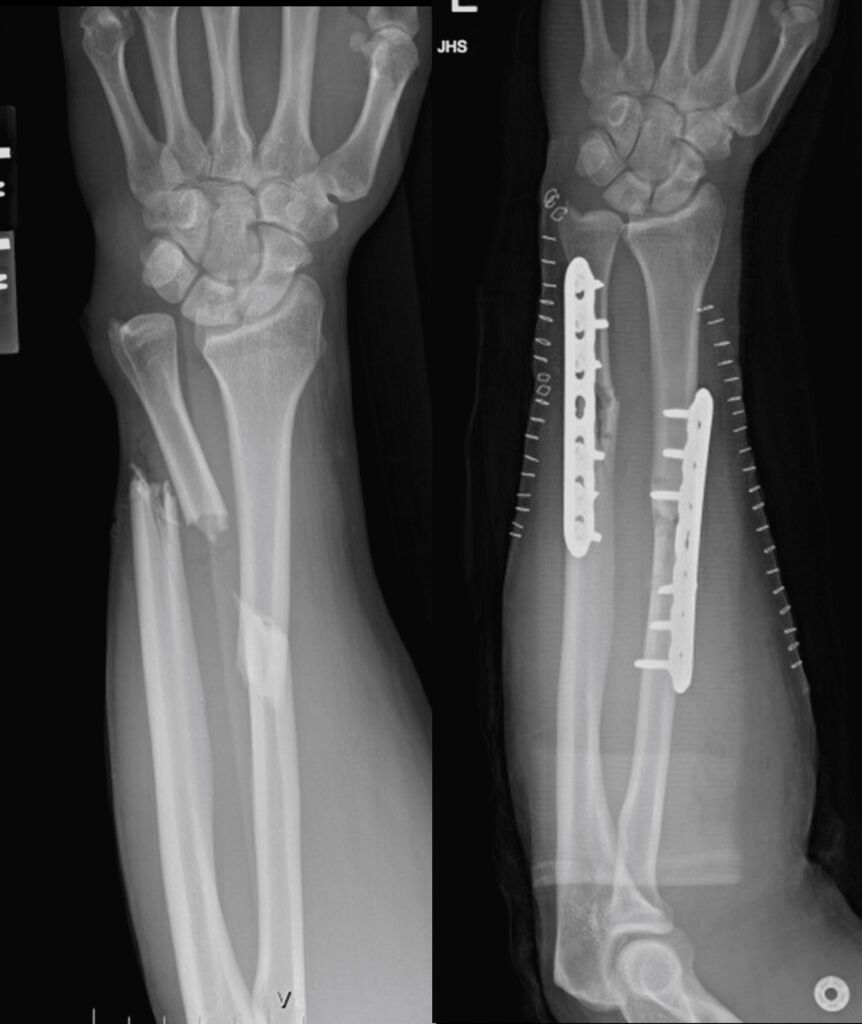

My son was seen for a broken arm. Everyone was very kind and patient with him, as this was a new experience for us. I am very pleased with the service we received and for a healed arm.